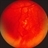

- Endophytic Vascular Hamartoma

- hamartoma, Von Hippel-Lindau

- 39 year-old Caucasian man with a diagnosis of Von Hippel-Lindau disease. Eyes were obtained post-mortem. Endophytic vascular hamartomas were identified in both eyes.